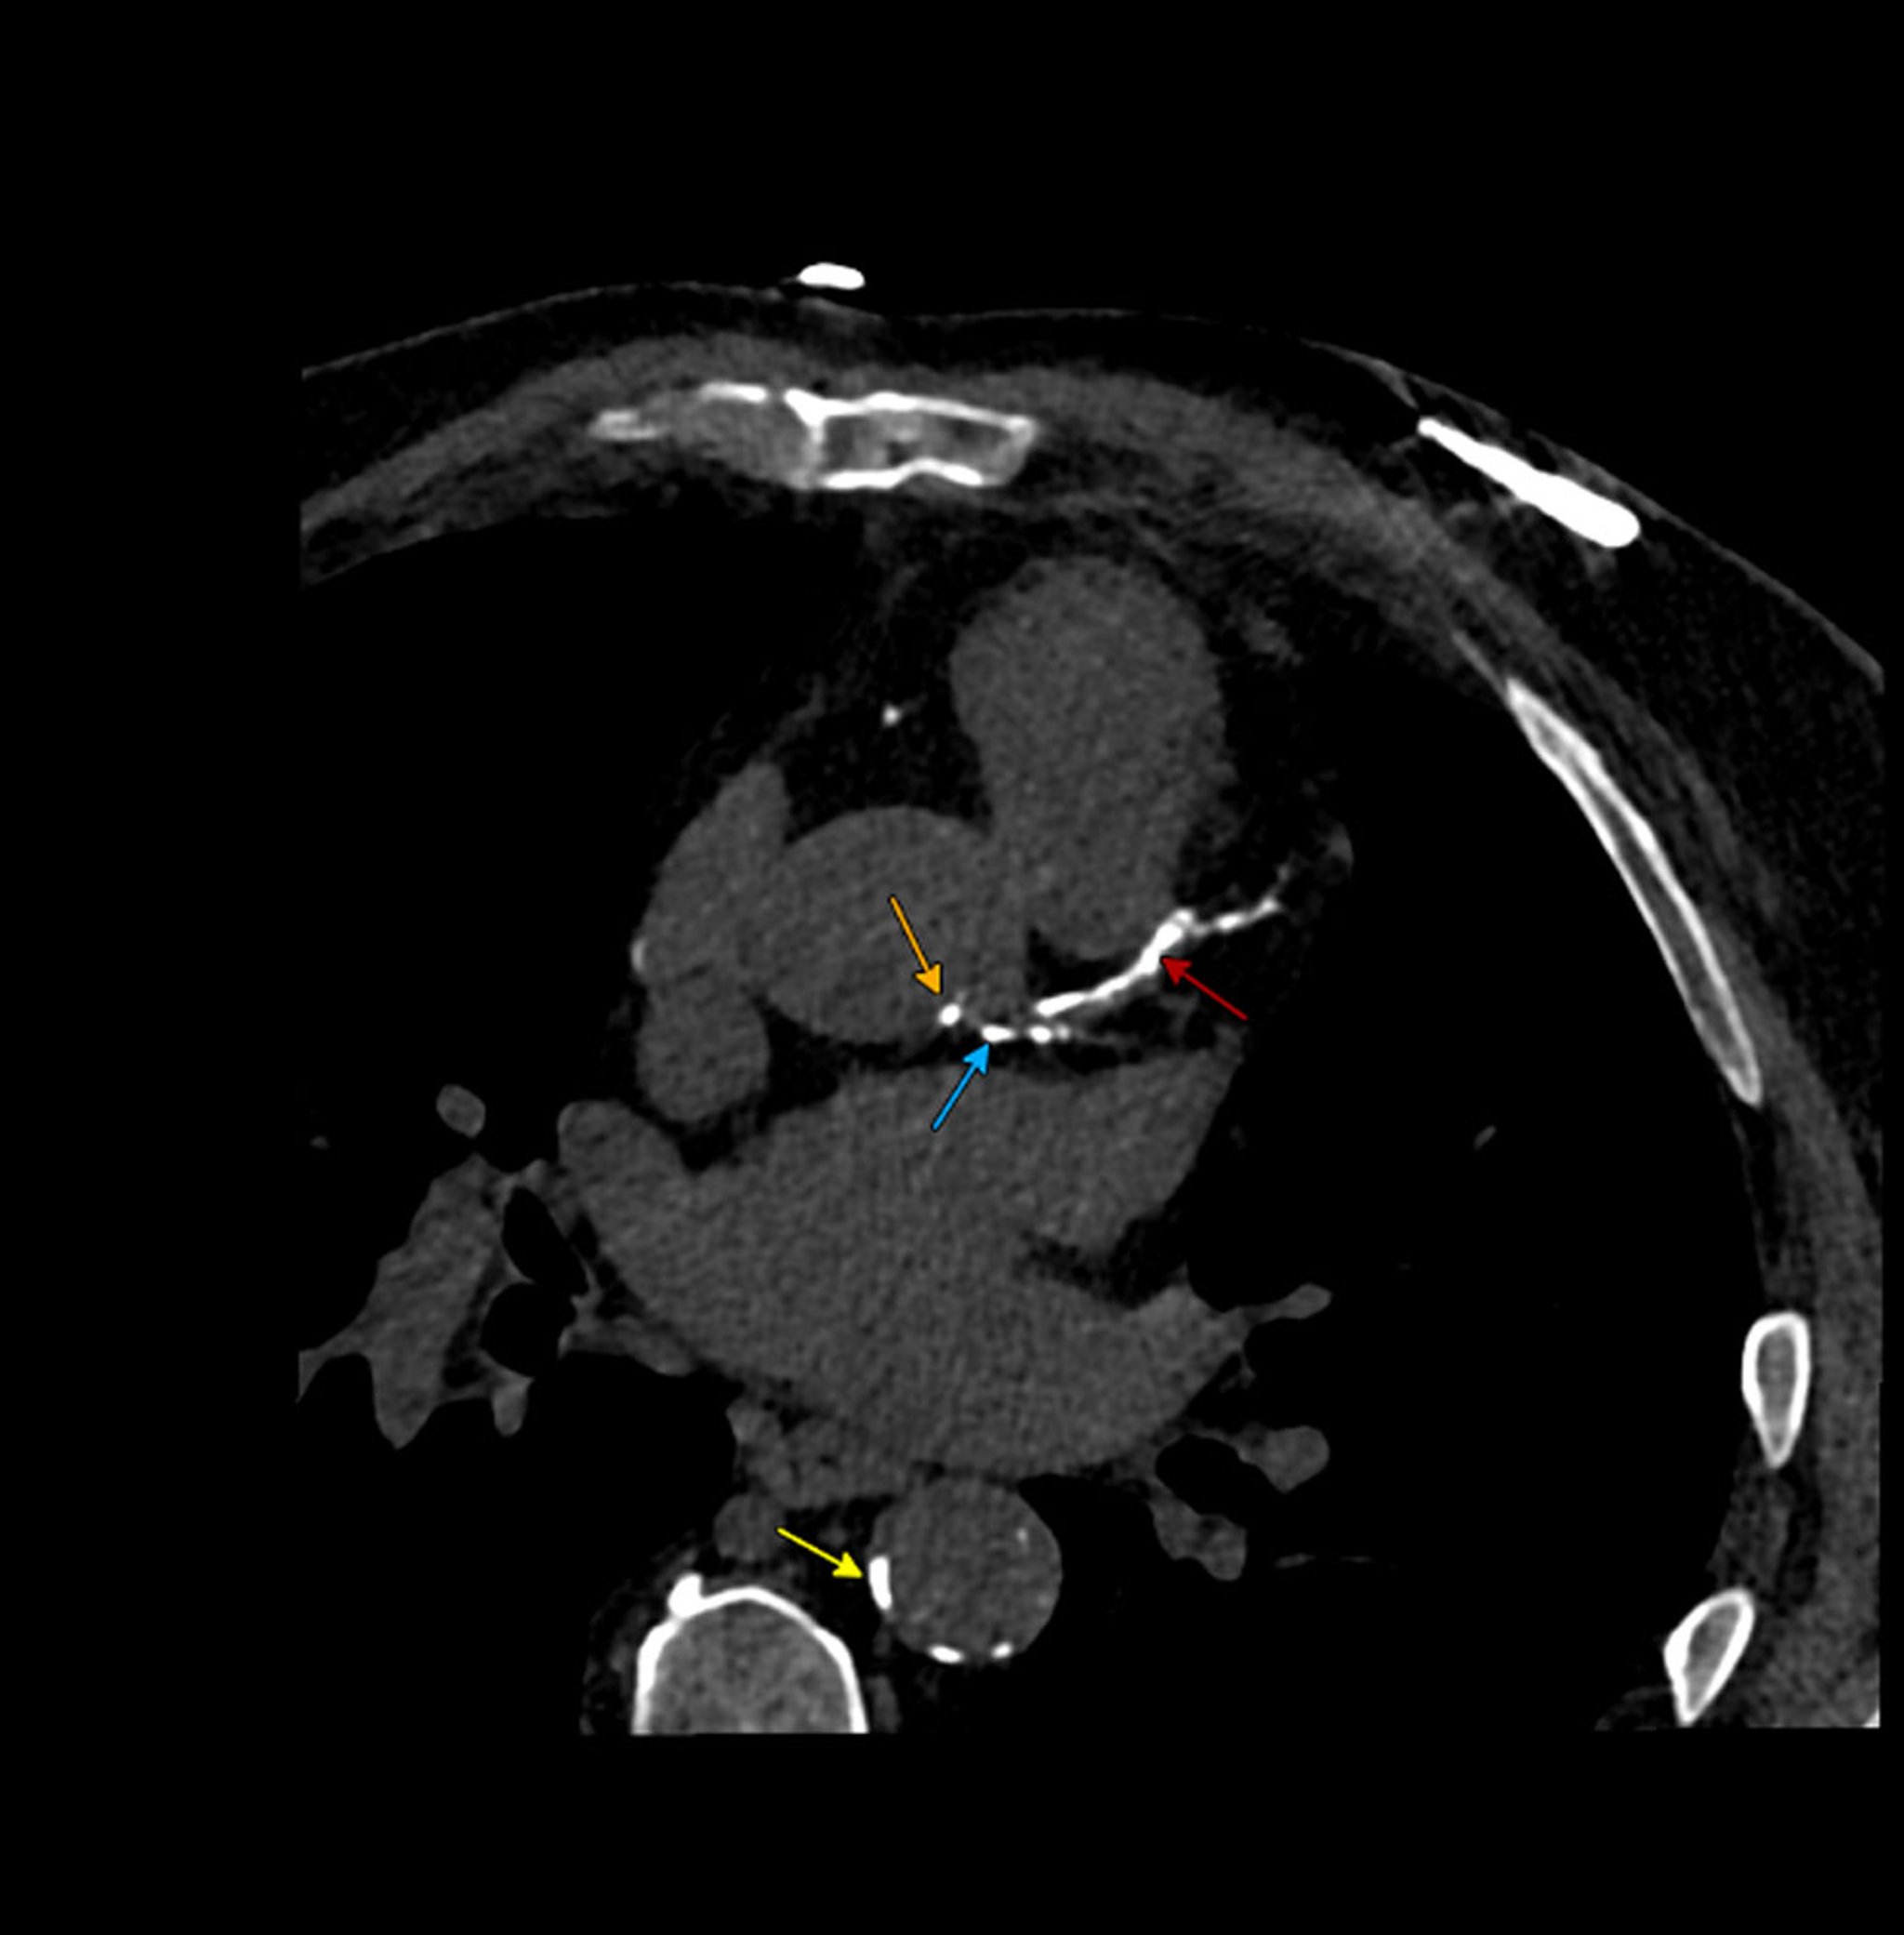

• AngioTC (ATC): A ATC utiliza TC com contraste iodado para avaliar a morfologia da placa aterosclerótica e detectar a gravidade da estenose com alta resolução espacial. Esta técnica envolve radiação ionizante e pode ser aplicada a qualquer leito vascular, tornando-a ideal para leitos vasculares pequenos e móveis, como as artérias coronárias.

• Imageamento molecular por tomografia por emissão de pósitrons (PET): esta técnica utiliza traçadores de imageamento molecular para detectar a atividade metabólica de placas ateroscleróticas (F18-fluorodesoxiglicose [FDG]) ou microcalcificações (F18-fluoreto de sódio).